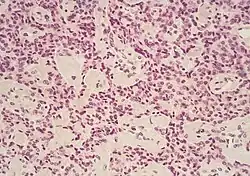

Micrograph of pancreatic ductal adenocarcinoma (the most common type of pancreatic cancer), H&E stain

Histopathology

The most common form of pancreatic cancer (adenocarcinoma) is typically characterized by moderately to poorly differentiated glandular structures on microscopic examination. There is typically considerable desmoplasia or formation of a dense fibrous stroma or structural tissue consisting of a range of cell types (including myofibroblasts, macrophages, lymphocytes and mast cells) and deposited material (such as type I collagen and hyaluronic acid). This creates a tumor microenvironment that is short of blood vessels (hypovascular) and so of oxygen (tumor hypoxia).[2] It is thought that this prevents many chemotherapy drugs from reaching the tumor, as one factor making the cancer especially hard to treat.[2][3]